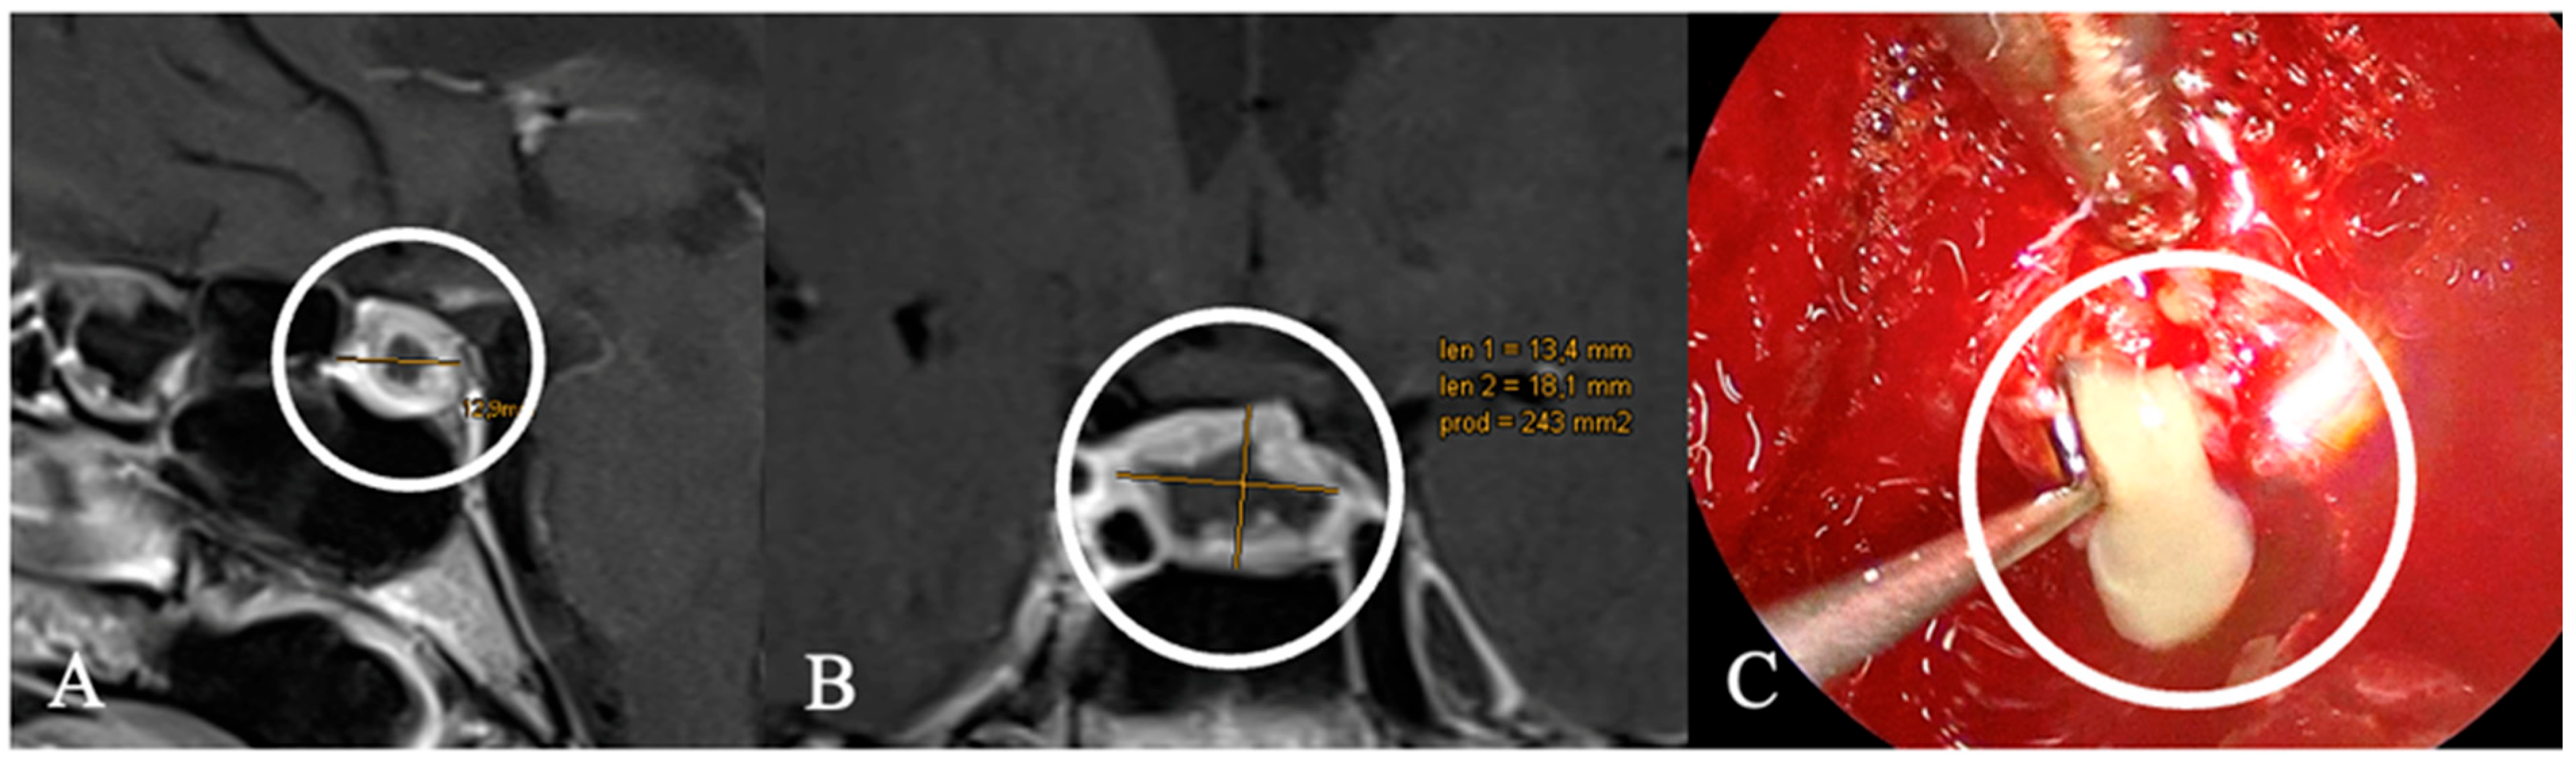

4.2. Differential Diagnoses and Case Presentations